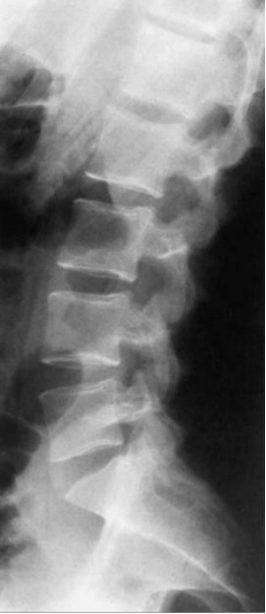

1.X光片

优势:检查速度快.费用低.辐射剂量小,可初步观察骨骼结构,如是否存在骨折.脱位.骨质增生.脊柱侧弯等。

局限:对椎间盘.神经根.肌肉等软组织显示不清,无法准确判断腰椎间盘突出.椎管狭窄等软组织病变。

适用情况:腰痛初步筛查,怀疑有骨骼损伤.退行性改变或外伤后排查骨折。